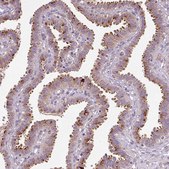

Monoclonal Anti-PCM1 antibody produced in mouse

immunoblotting: 1 μg/mL, immunohistochemistry: 1:200- 1:500

Pericentriolar material 1 (PCM1) gene codes for a 228 kDa protein. It has various coiled-coil domains in its amino-terminal. It is located in the cytoplasmic granules and is termed as centriolar satellites. PCM1 is located on human chromosome 8p22.

• IHC tissue array of 44 normal human tissues and 20 of the most common cancer type tissues.